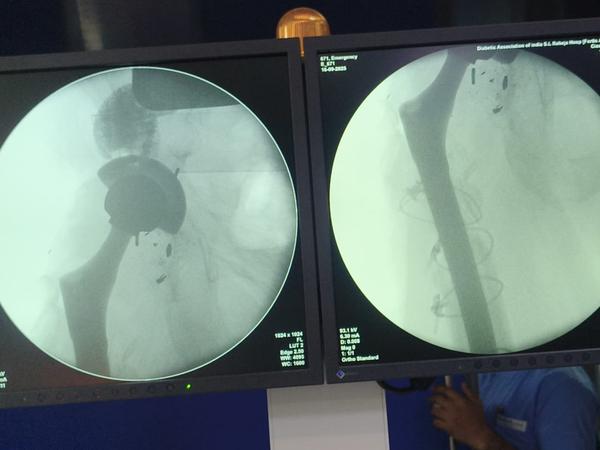

Revision Hip And Knee Replacement

Dr Randive has 25 years experience in Revision Knee and Revison Hip Replacement surgeries. It took him more than 25 years of training hard work and thousands of surgeries to achieve excellence in Revision Knee and Hip Surgeries. He has successfully achieved this milestone through extensive training.